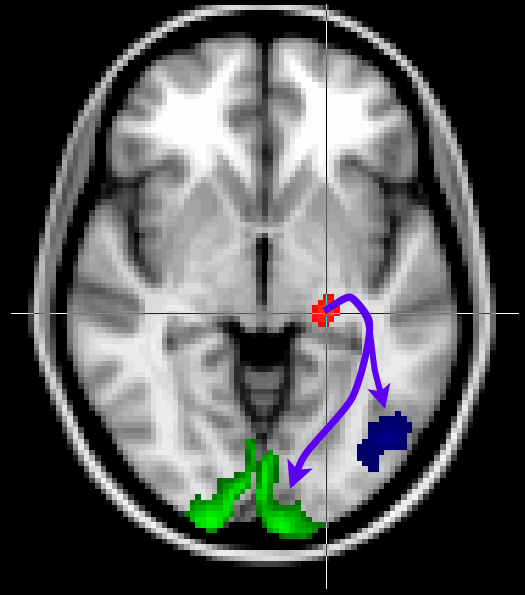

Here we will segment the thalamus based on the connectivity with the cortex. To do this we will need to estimate for every voxel in the thalamus how strongly it is connected with a number of pre-defined ROIs in the cortex.

seed_thal_right is the seed mask and should cover the right thalamus. From each voxel in this mask we are going to measure the number of streamlines connecting to the cortical regions, which are defined by the other masks. To run this analysis, in the Fdt GUI:

The objective of this type of analysis is to ask the following question: For each location in the seed mask, what is the relative probability of connection to each of my target masks? The output is therefore a single image for each target mask in which only voxels within the seed mask contain data. At each voxel within the seed mask the voxel value is the number of streamlines which reached this target mask from this seed voxel. These outputs can be found in the output directory as the seeds_to_* files. Unfortunately, 10 streamlines is not enough to get a reliable segmentation of the cortex, so we ran for you the same tractography with 2000 streamlines per voxel, which is available as the THAL2CTX_right directory.

Now overlay in FSLeyes, in turn, each of the seeds_to_* files in THAL2CTX_right. Compare the spatial distributions and probabilities of connection from different thalamic voxels to different cortical target zones. Do you see any overlap between connectivity probabilities of the different targets in the seed region? What do you think this means? Answer.

Run find_the_biggest on the outputs of seeds to targets to generate a hard segmentation of the thalamus and overlay this segmentation onto the standard brain. Something like:

find_the_biggest THAL2CTX_right/seeds_to_* biggest_segmentation

The different numbers in the output image (biggest_segmentation) each relate to a different target mask. You may want to change the colour map to something like Random.